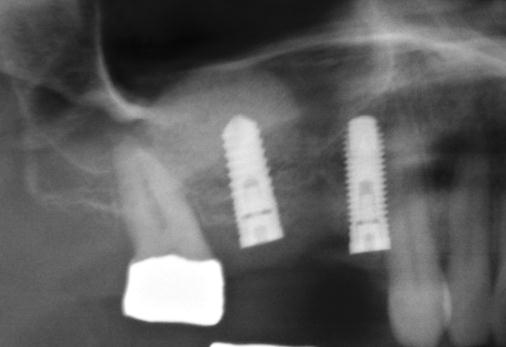

Sinus lift

Nejčastější oblastí pro doplnění kosti je čeleni dutina horní čelisti.

Tento výkon se nazývá sinus lift - aplikace kostního granulátu do čelistní dutiny

Jedná se o vyzvednutí membrány, která čelistní dutinu vystýlá, pod vyzvednutou membránou vznikne kapsa, kam se umístí augmentační materiál, do kterého se zavedou implantáty.

Vhojení implantátů se při této operaci prodlužuje na 6-12 měsíců.

Souprava pro laterální přístup k sinus liftu, speciálně navržena pro bezpečný a méně invazivní laterální přístup k nadzdvihnutí membrány sinu. LAS Kit nabízí v závislosti na anatomii dutiny ústní a plánech operace různé využití.

CAS Kit

Souprava pro krestální přístup k operaci sinus liftu tím, že se vytvoří v kosti kónický odštěpek, kterým lze membránu bezpečně nadzvednout.